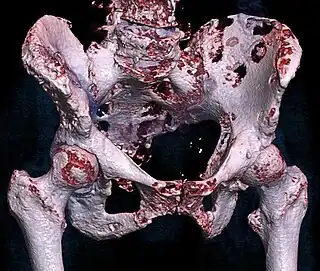

![]() | |

| 3D rendered CT scan of bone metastases of the hip bone, in a 60 year old woman with parotid gland cancer. Large lesions are seen on the hip on the more distant side. Involvement of the spine has caused a compression fracture. | |

CT scan: Parotid gland cancer spread to hip. -